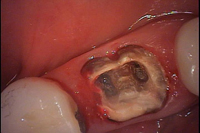

• 古い詰め物・被せ物・歯の土台の除去とむし歯の除去

古い詰め物・被せ物・歯の土台等を取り除いた歯

古い詰め物・被せ物・歯の土台等を取り除き、虫歯を除去したうえで、残る健康な歯を診断し、歯を残せるかどうか診査します。